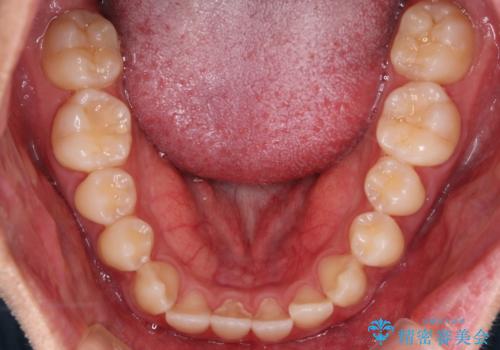

心配していた歯肉退縮も起こらず、前歯の噛み合わせと歯並びが綺麗に改善されました。

期間も1年2ヶ月と短期間で終了することができ、とても満足度の高い治療になりました。